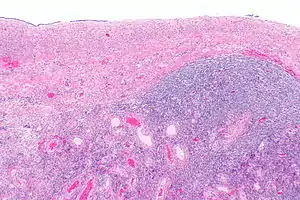

| Ovarian serous cystadenoma. The cystic space is at the top of the image. Ovarian parenchyma is seen at the bottom right. H&E stain. | |

Serous cystadenomas are diagnosed by histomorphologic examination, by pathologists. Grossly, they are, usually, small unilocular cysts that contain clear, straw-coloured fluid. However, they may sometimes be multilocular. Microscopically, the cyst lining consists of a simple epithelium, whose cells may be either:[3]

- be columnar and tall and contain cilia, resembling normal tubal epithelium

- be cuboidal and have no cilia, resembling ovarian surface epithelium